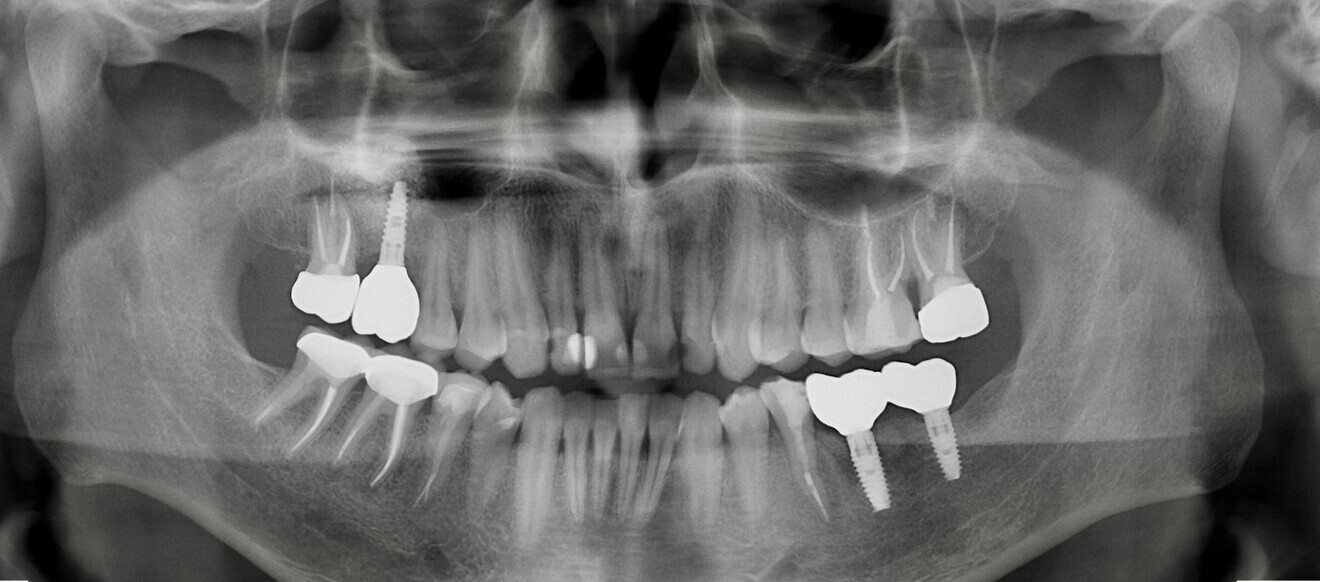

Fig. 1 : Situation préopératoire, montrant la zone concave entre les implants, favorisant la rétention de résidus alimentaires et la péri-implantite.

Le patient, 47 ans, présentait une résorption importante de la crête alvéolaire postérieure mandibulaire résultant de l’extraction des molaires (Fig. 1). Une récession gingivale péri-implantaire avec présence d’un tissu kératinisé minimal (moins de 1 mm) a été diagnostiquée au niveau de deux sites postérieurs. Le conditionnement des tissus mous péri-implantaires a été effectué quatre mois après la chirurgie implantaire.

Fig. 20 : Radiographies prises en 2017.

Fig. 21 : Radiographie prise  en 2019.

Fig. 22 : Radiographie  prise  en 2022.